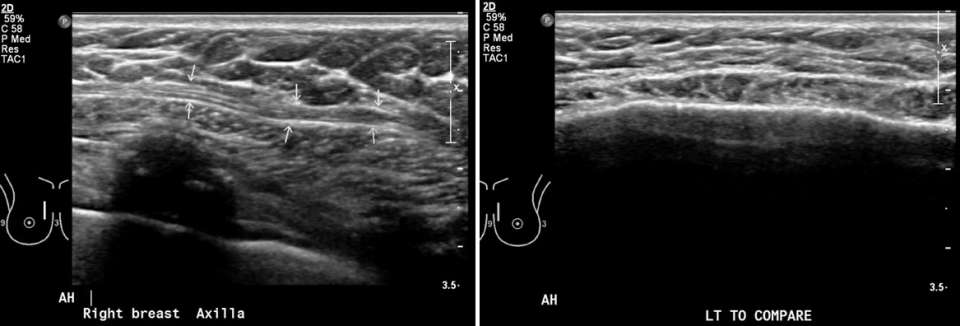

Ultrasound Appearance

Ultrasound imaging of the sternalis muscle reveals a well-defined, hypoechoic structure with internal striations, consistent with the appearance of skeletal muscle. Ideally, its continuity with chest wall muscles can be traced to prove muscular origin. In cases of suspected unilateral sternalis muscle, comparison ultrasound can be obtained of the contralateral chest to demonstrate asymmetry of the chest wall musculature.